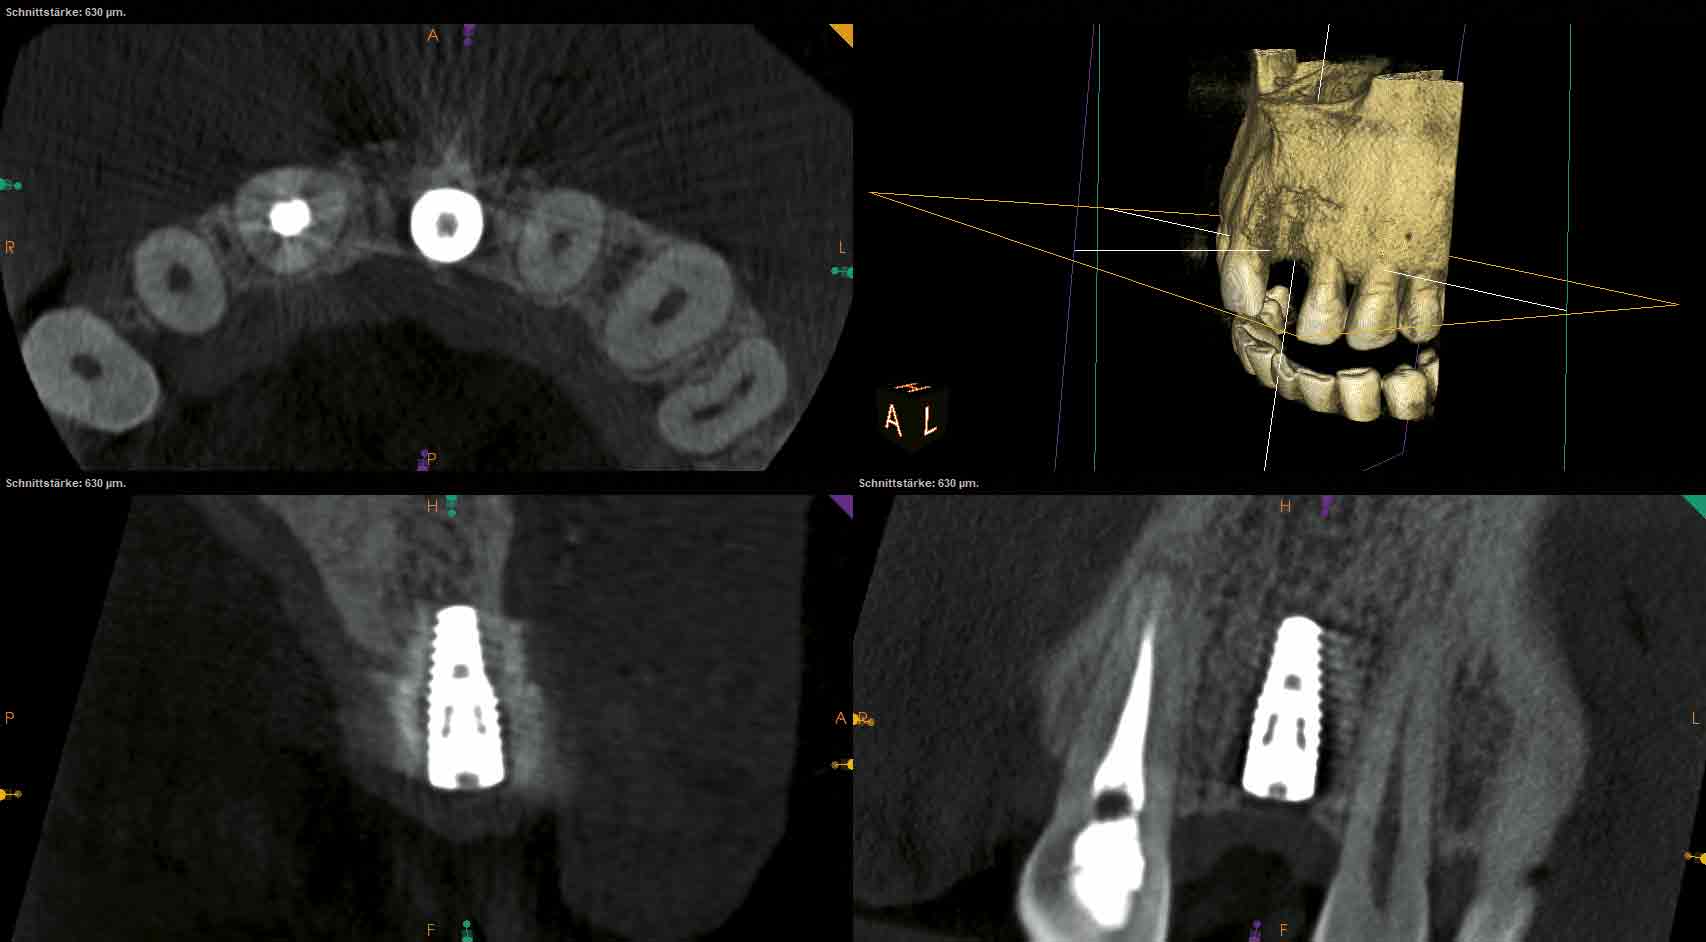

14/18 - CBCT scan after implantation

Block augmentation with maxgraft® and cerabone® – PD Dr. Dr. F. Kloss